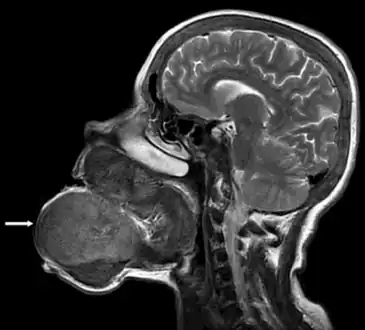

Image showed that the brown tumor originated from the mandibular and maxillar bones

Micrograph of a brown tumor (left of image). H&E stain.